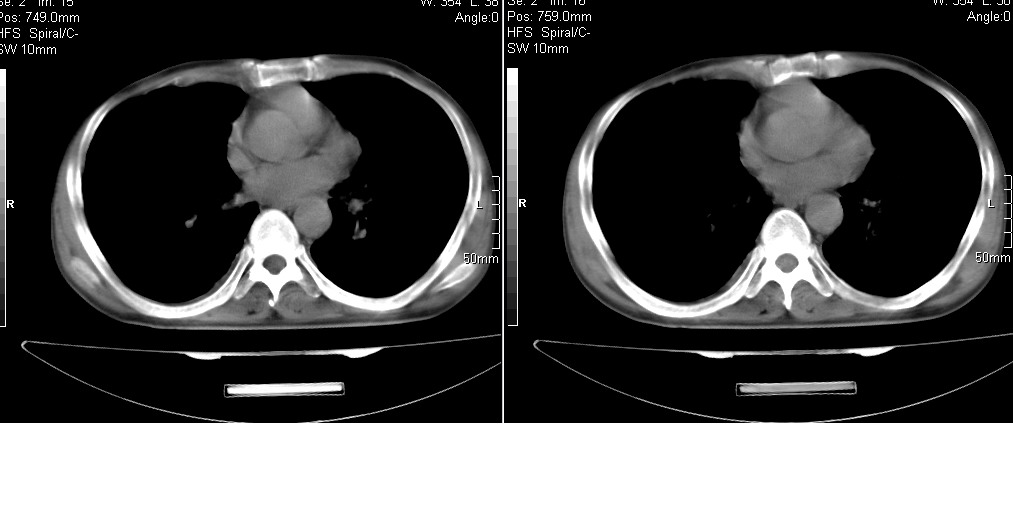

以下是引用光线在2008-5-6 18:36:00的发言:[br]双肺结核(左上肺空洞形成)、间质性改变合并感染,右肺大泡;右侧胸膜增厚。

以下是引用zsl6918在2008-5-7 1:54:00的发言:[br]首先肺泡蛋白质沉着症,其次考虑机遇性感染。